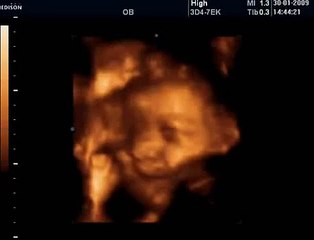

www.cemturan.combr www.dr-cemturan.combr www.jinekolojikonkoloji-istanbul.combr www.perinatoloji-istanbul.combr Hamilelikte renkli Doppler ultrason niçin yapılır? Bebek renkli mi görülür yoksa damarları görmek için mi renkli Doppler yapılır? Prof. Dr. Cem Turan'dan izleyin. Renklli doppler ultrason ile en çok incelenen damar bebeğin göbek kordonundaki damarlardır (umblikal damarlar). Bunun dışında rahim damarları, beyin damarları, kalp damarları gibi çeşitli damarlar incelenebilir. Özellikle rahim içerisinde gelişme geriliği (iugr) şüphesi olan bebeklerde, anomali varlığında, kalp ritm bozukluğu veya kardiyak anomali varlığında, yüksek tansiyon hastalarında yapılır. Her gebelikte rutin olarak yapılan bir inceleme değildir.